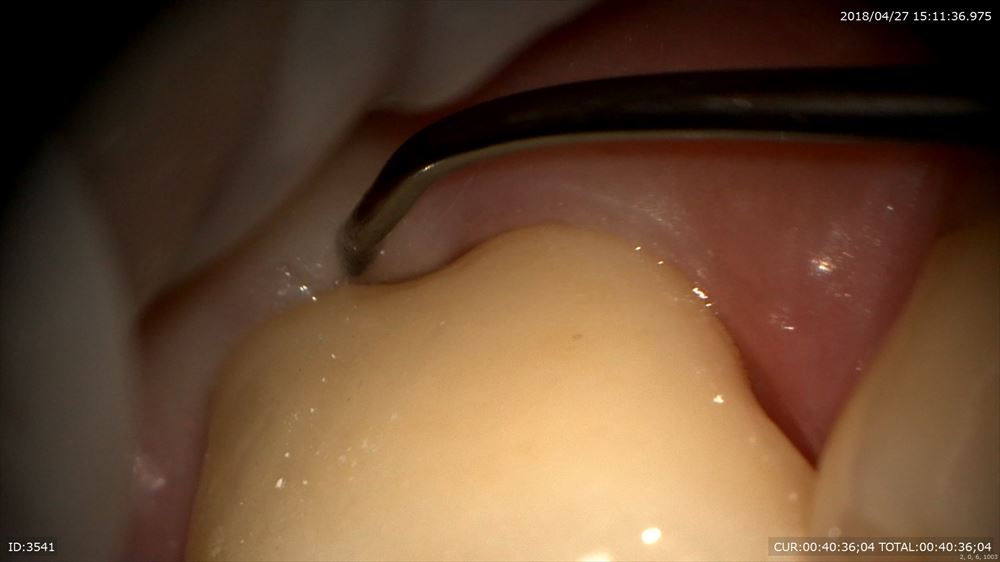

きつさの調整

吸い込まれます。ここから

吸い込まれた

25倍でフィットの確認

スムーズ